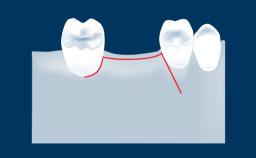

A incisão relaxante periosteal, ou IRP, é uma técnica cirúrgica oral comum realizada para aumentar a mobilidade de um retalho cirúrgico. Quando realizada corretamente, a incisão relaxante periosteal permite que o retalho seja avançado coronariamente para que o fechamento primário sem tensão da região da cirurgia seja possível.